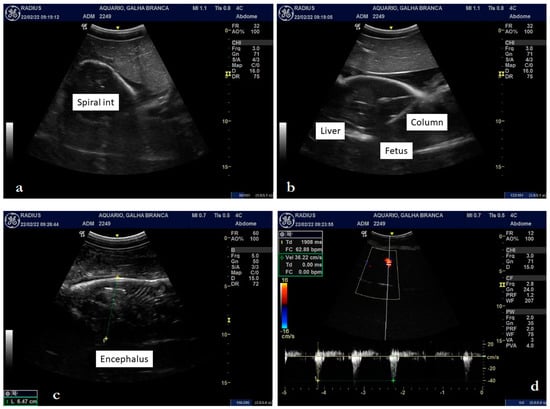

Ultrasound Examination

3.2. Internal Morphology